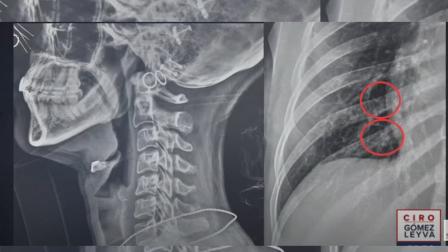

*Tamara Acuña, cineasta, terminó con un esguince cervical y dos costillas rotas tras ser agredida en la marcha del 8 de marzo

La joven terminó con dos costillas rotas y un esguince cervical. A pesar de las agresiones que sufrieron Nicole y Tamara en la conmemoración del Día Internacional de la Mujer, aseguran que el miedo no las frenará para volver a protestar por la violencia contra la mujer.